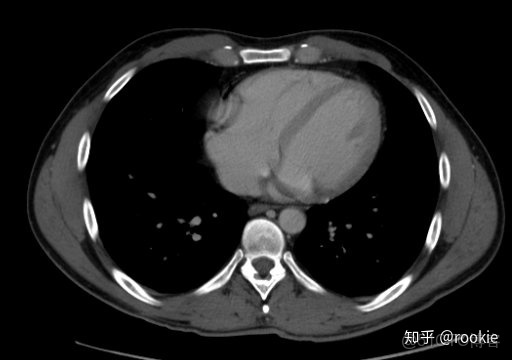

縱隔窗口窗口設置: (W:500,L:50)優點: 這些設置在本質上與軟組織設置或腹部設置相似,並進行了微調,以儘可能清晰地顯示出縱隔病理。

CLAHE算法增強局部對比度的X光圖像增強效果對比_#python 計算對比度_13

縱隔窗與腹部或軟組織窗相似,但稍作調整以顯示縱隔結構。

CTA窗口窗口設置: (W:600,L:170)或(W:650,L:225)優點: 在評估CT血管造影研究(或在血管中具有明顯對比的CT掃描的任何階段)時,此設置可用於嘗試清晰地觀察血管病變。它在提供目標血管信號的同時具有良好的平衡,而無需血管內的亮度過高會沖洗腔內病變。

CLAHE算法增強局部對比度的X光圖像增強效果對比_ico_14

此窗口用於在感興趣的血管中有相當大的對比度的情況下(例如CT血管造影)。